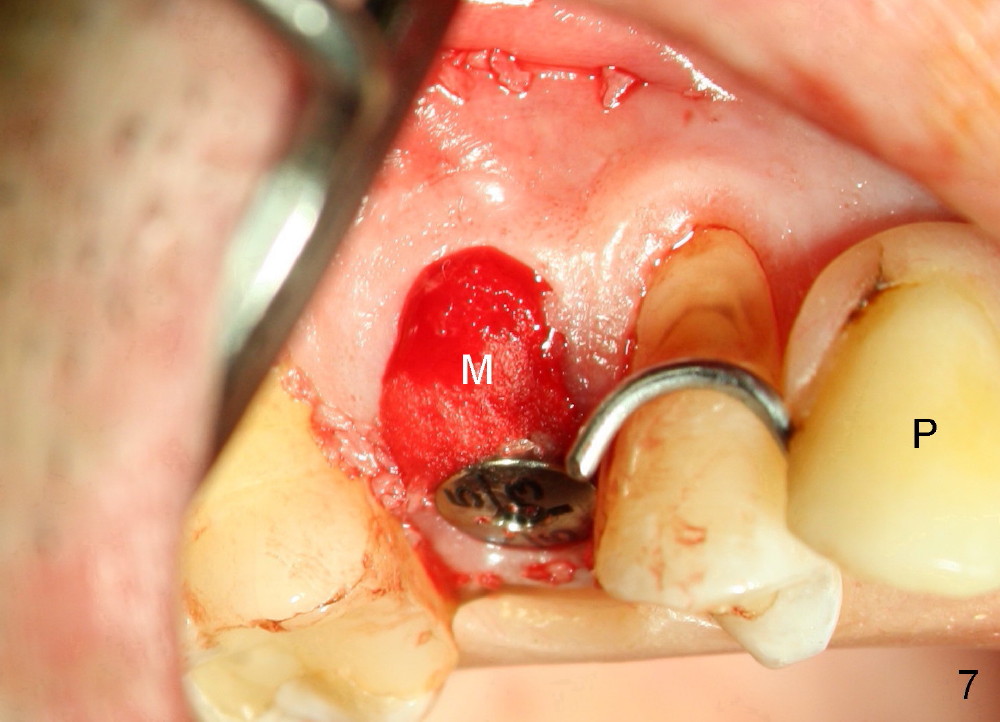

A 51-year-old man has several missing teeth in the maxilla restored by a partial denture. The tooth #4 fractures (Fig.1) and is planned to be restored by an implant (Fig.2 design: 4.5x14 mm). Immediately post extraction, osteotomy is initiated by a 2.0 mm pilot drill at the depth of 14 mm (3 mm into new bone, Fig.3). Finally a 4.5x14 mm SM (submerged) implant is placed with insertion of a 5.2x5(3) mm healing abutment (Fig.4). Mixture of autogenous bone and demineralized cortical allograft is placed in the gap between the buccal plate and the implant/abutment (Fig.6), covered by collagen membrane (Fig.7 M; P: partial denture). In fact the membrane is fixed between the implant and the healing abutment lingually. The wound is finally covered by perio dressing (Fig.5 ^). The patient returns 5 days postop. The perio dressing is removed unintentionally. It appears that the membrane has started to be resorbed (Fig.8).